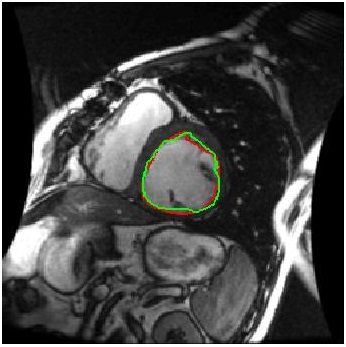

We train our ISR network from scratch. Each volume slice is treated as a separate image and transformed by random rotation and translation. We rotate the images between in steps of . For each rotation we translate the image by pixels in steps of . Thus on an average we get transformation for each image. Thus an average of slices per image gives a total of cardiac MR images. We show results on ISR for scale factor . Results for ISR are summarized in Tables 5. Following the approach for retinal landmark and pathology segmentation, we also show results for cardiac left ventricle segmentation (Table 6). For each segmentation approach we employ UNets as the segmentation framework and show results for different super-resolution methods as well as the low-resolution images (). Dice metric values for segmentation accuracy are shown in each case. Similar to retinal pathology segmentation we extract a patch covering the pathology and apply super-resolution for scale factors .

Figure 6 shows results for segmenting the cardiac LV from MRI. For each case we present results on the original HR images, SR images obtained by each of the methods being compared and also when using the LR images (scale factor ). It is quite obvious that the LR images are very fuzzy and don’t give accurate information on the anatomical boundaries. On the other hand the SR images from our method can predict a highly accurate reconstruction of the actual image. Other ISR methods show some degree of blur in the SR images. It is remarkable that deep neural network based methods are able to reconstruct original high quality images despite limited information in LR images. This is possible because of the ability of the generator networks to learn the relation between HR and LR images.